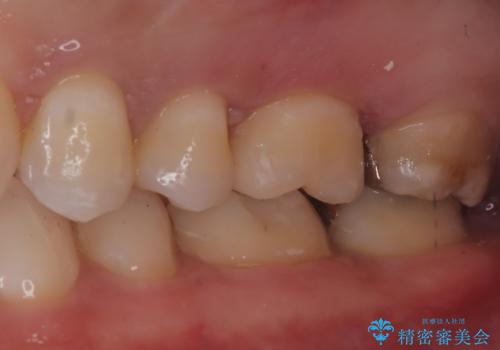

【セラミックインレー】歯科検診にて虫歯発見。

- 定期健診にて虫歯を見つけたためセラミックインレーにて修復しました。

綺麗に仕上がり患者さんも非常に満足されていました。

当院でのセラミックインレーはラバーダム防湿をして接着しております。